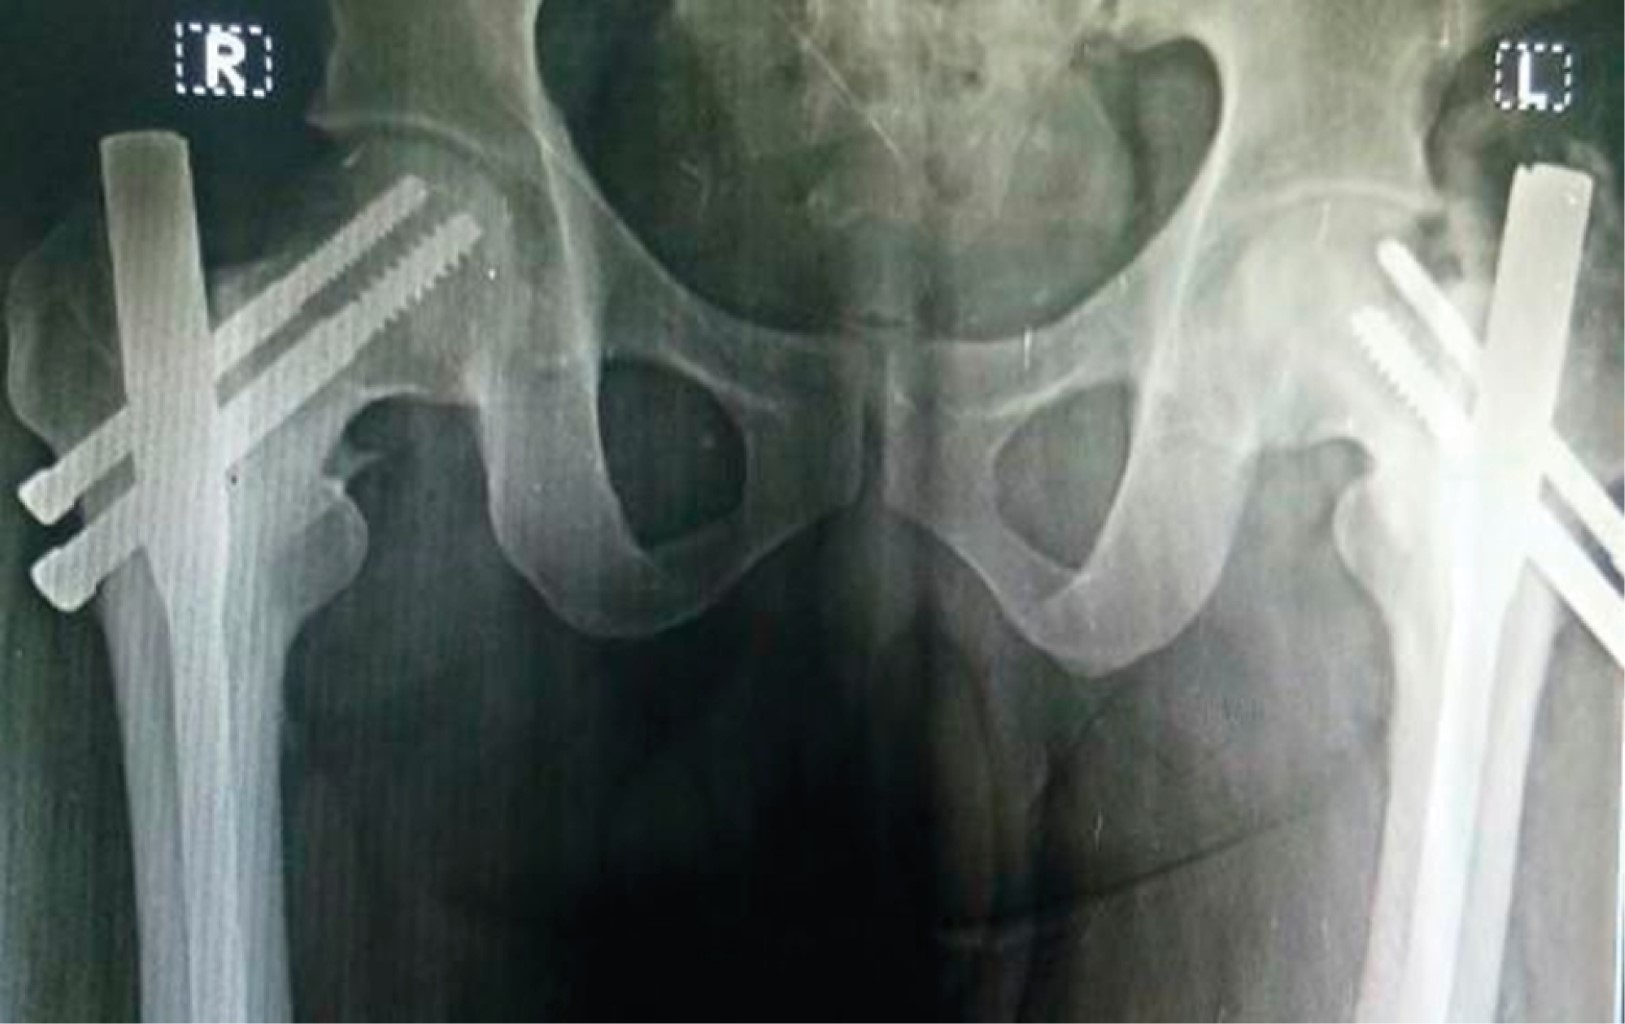

Implant related complications like screw back out (Figure 1), guide wire breakage (Figures 2 and 3), Z effect (Figure 4), TAD outliers (Figure 5) were more in PFN group whereas lateral screw protrusion, locking mechanism failure and barrel disengagement was more in PFNA2 group as shown in Figures 6, 7, 8 and 9. Neck shaft valgus outliers are more common in PFN group (Figure 10).

We observed nearly double the number of complications in the PFN group compared to the PFNA2 group, with implant-related complications constituting a significant portion, reinforcing findings from previous studies.20,21,22,23 Gardenbroek et al. found that the risk of secondary late complications and reoperation is much higher with PFN than with the helical blade device.20 Overall, implant-related complications were 34% in the PFN group.7,20,21,22,23

Implant-related complications, such as screw back-out, guidewire breakage, and proximal protrusion, were more pronounced in the PFN group, whereas lateral screw protrusion and medial migration were notable in the PFNA2 group.24 Lateral screw protrusion was observed in four patients in the PFNA2 group and one patient in the PFN group at the final follow-up in our study. Hu et al suggested a morphological mismatch in the Asian population between the proximal fragment of PFNA2 and the greater trochanter, leading to post-operative lateral trochanter pain.24